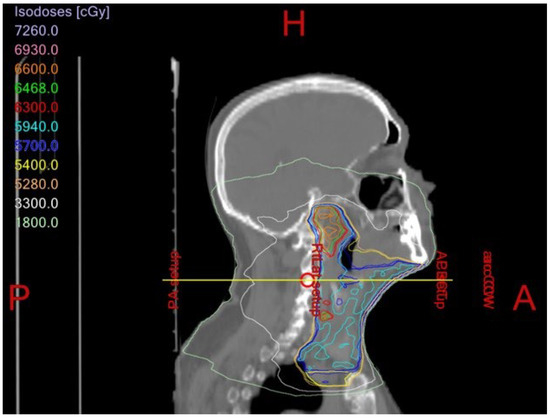

1.3. Xerostomia/Hyposalivation

Prevention and Management of RT-Induced Xerostomia